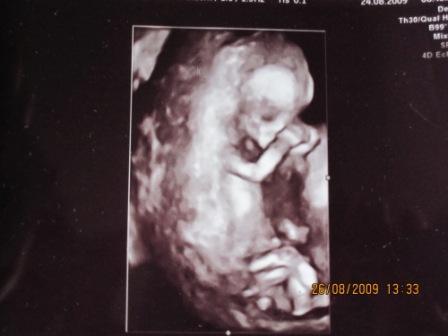

Erstmal muss ich sagen dass ich etwas enttäuscht von meinem FA war, da er mich am Montag sehr schnell "abgefertigt" hatte. Das kenn ich so gar nicht vom ihm, schließlich war seine letzte VU ganze 7 Wochen her. Er hatte mir erklärt dass er wenig Zeit hat, weil es sein erster Tag nach 3 Wochen Urlaub war und es über die Sommerferien hier wohl einen Baby Boom gab weil plötzlich wohl aussergewöhnlich viele schwanger sind. Hab ich zwar Verständniss für, aber ich dachte dass ich wenigstens meinen Mutterpass bekomme, aber nee den gibts erst in 2 Wochen. Grummel, dann bin ich schon 15. Woche find ich eigentlich viel zu spät. Naja Ultraschall hat er gemacht, Gummibärchen ist schon richtig groß geworden: 5,6cm Bildchen hänge ich an, ich hab auch ein 3D Bild bekommen, versuche ich auch mal hochzuladen LG Jana